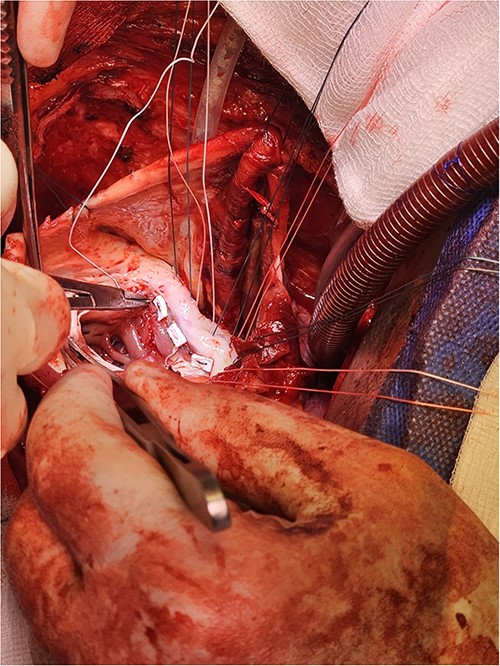

Following median sternotomy, cardiopulmonary bypass was instituted (bicaval drainage, ascending aortic return). Antegrade cardioplegia was delivered with aortic root venting and bicaval snaring. Dense adhesions surrounded the aneurysm, which had a thin wall, measured ⁓15 cm from LV apex to mitral annulus, and contained around 150 g of clot. The posterior mitral leaflet appeared retracted, preventing coaptation due to LV stretching. The aneurysm was resected (Fig. 2), and the LV wall repaired with a 5 × 3 cm patch, restoring normal LV size (Fig. 3). The musculotendinous junctions of the anterior and posterior papillary muscles were approximated using pledgeted 3–0 polypropylene sutures (Fig. 4). The patch repair was completed (Fig. 5), and the overlying sac oversewn for haemostasis.

A: The patch was parachuted down and secured. B: Following this the aneurysm sac was closed over the patch for added haemostasis.